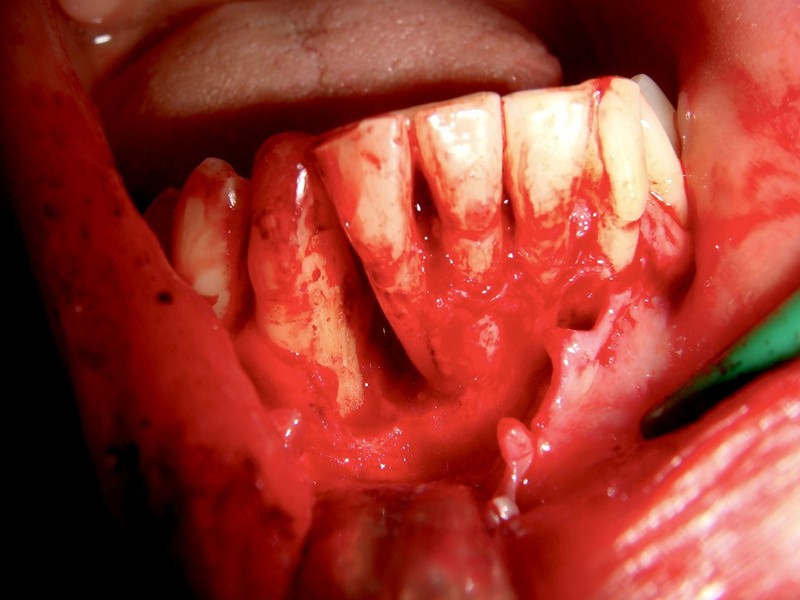

Rigenerazione Gravi difetti parodontali

Rigenerazione difetto parodontale di un canino inferiore con materiale eterologo

rigenerazione grave difetto parodontale a carico del 46

rigenerazione grave difetto parodontale a carico una intera emiarcata